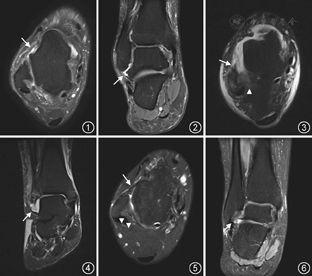

LCL损伤患者共26例,其中单纯ATFL损伤19例(ATFL部分撕裂8例,断裂9例,陈旧损伤2例),单纯CFL损伤1例,ATFL合并CFL损伤3例(图1,图2),ATFL合并CFL、PTFL损伤3例(图3,图4)。

ATFL在轴位MR图像观察最佳,在腓骨远端可见向前内侧走形的细长韧带结构,T1WI序列和PD压脂序列均表现为均匀线状低信号,其外侧紧邻皮下脂肪。通过对志愿者正常踝关节MRI的分析,发现所有志愿者的ATFL均可在3层轴位图像内显示,并至少有一层图像可完整显示ATFL全程(图5)。26例踝关节韧带损伤中,涉及ATFL损伤25例(单纯ATFL损伤19例,ATFL合并CFL损伤3例,ATFL合并CFL、PTFL损伤3例),MRI正确诊断25例,漏诊ATFL陈旧损伤1例。急性ATFL损伤表现为韧带增粗、信号增高或连续性中断、腓骨附着端撕脱骨折,断端收缩、扭曲,并可见腓骨、距骨附着端骨髓水肿(图1,图3)。慢性ATFL损伤可表现为韧带增粗或纤细,并可见韧带周围积液。